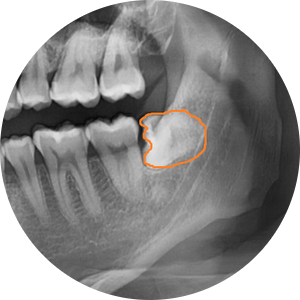

이 치아는 예쁘게 올라왔네요~

그냥 잡고 뽑으면 끝이겠죠~?

시간도 앞에 치아보다는 빨리 뽑겠어요~